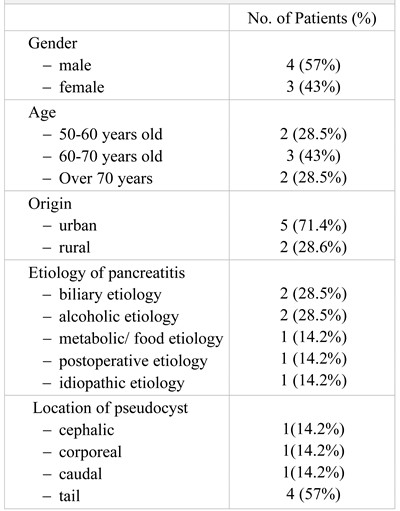

An abdominal CT is performed which reveals bilateral pleurisy, left basal pulmonary condensation, pseudocyst in the tail of the pancreas whose dimensions were 9/8 cm, multiple cystic images located in the left renal bed and small hepatic hypodense node (Figure 1).

Figure 1.

The CT exam revealed a 4-cm diameter pancreatic pseudocyst in the tail of the pancreas.